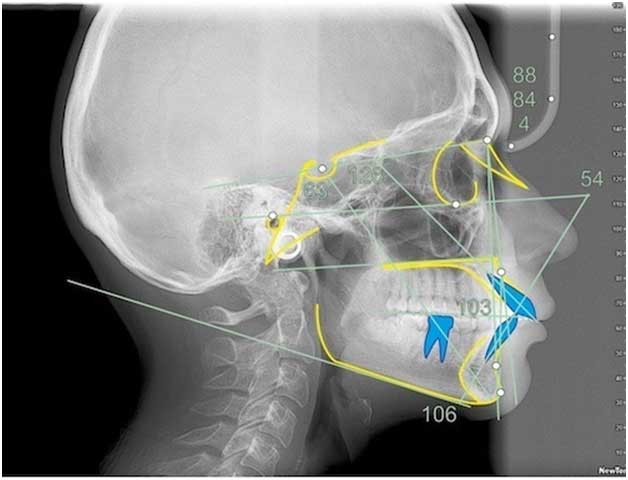

Расчёты «красивого профиля»